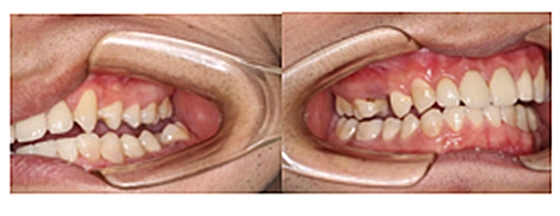

下面是醫(yī)生眼中和ct下的我們

一身病痛啊

牙結石、牙齦炎癥、牙體殘缺、慢性牙髓炎、蛀牙......

才二八芳華的我們

已經(jīng)滿目蒼夷

再來看看曾經(jīng)的我們